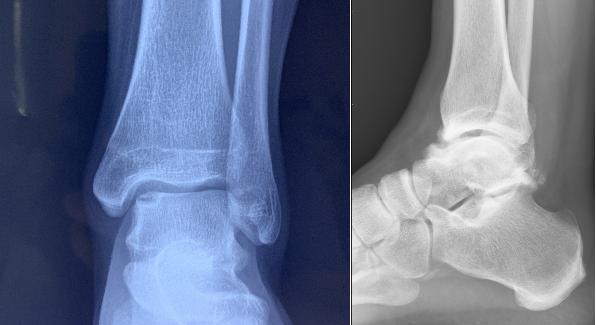

从 X 光片上,我们只能看到踝关节的骨性的结构,这也是为什么有时候医生会要求再做核磁共振的检查来看看踝关节的周围,韧带、肌肉以及肌腱的情况。